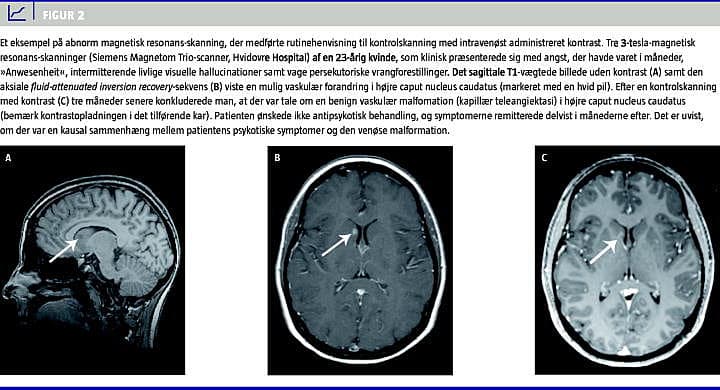

Hovedfundet er, at man med rutinemæssig CT kan detektere abnormiteter, som potentielt kan forklare patientens symptomer i omkring 0,8% af FEP-patienterne. Med MR-skanning kan abnormiteter påvises i omkring 3,3% af patienterne. Abnorme fund fører i enkelte tilfælde til videre udredning, men patientens behandling beskrives overordnet som uændret (se Figur 2). Akut behandlingskrævende intrakraniel patologi er ikke rapporteret som følge af rutineskanning.

I 1988 undersøgte Battaglia og Spector [9] 45 FEP-patienter med CT. Tre patienter havde mindre neurologiske udfald ved klinisk undersøgelse: ventresidigt dobbeltsyn (n = 1) og hyperrefleksi på højre underekstremitet (n = 2), hvoraf en havde ekstensivt plantart respons. I alt 42 skanninger var normale (også hos de tre patienter med neurologiske udfald). Tre CT'er var abnorme (se Tabel 2 for detaljer). Ingen af fundene havde umiddelbare kliniske konsekvenser. Det skønnes muligt, men er usikkert, om det fundne infarkt i nucleus caudatus var kausalt (Figur 2 ).